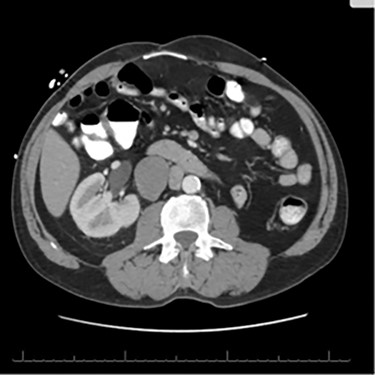

A 56-year-old male with a history of left testicular cancer treated with chemotherapy (Bleomycin, Etoposide, Cisplatin; BEP), radiotherapy, retroperitoneal lymph node dissection, and partial left nephrectomy in 1992 presented to hospital with complaints of left lower abdominal mass for 3–5 years, associated with ulceration and active drainage. He was asymptomatic with β-hCG and alpha-fetoprotein (AFP) levels within reference ranges (<2.39 and 1.4, respectively). On examination, inspection of abdomen revealed well-healed midline scar with bilateral incisional hernias and a 10 × 8 cm mass in the left lower quadrant (Fig. 1) firm and fixed to the abdominal wall. An open lesion characterized by yellow, non-purulent drainage was noted in the left lower quadrant. CT imaging of abdomen and pelvis with contrast revealed a multiloculated large cystic mass in the left inguinal canal measuring 11 × 7 × 7.7 cm (Fig. 2) along with a similar soft tissue nodule in the right inguinal area. A right retroperitoneal soft tissue mass in the mid abdomen was also identified, measuring 3.3 × 4.2 × 5.7 cm (Fig. 3). Changes of prior left nephrectomy and orchiectomy consistent with treatment of previous left-sided testicular cancer were also noted.

CT imaging abdomen and pelvis with contrast revealed a multiloculated large cystic mass in the left inguinal canal measuring 11 × 7 × 7.7 cm.